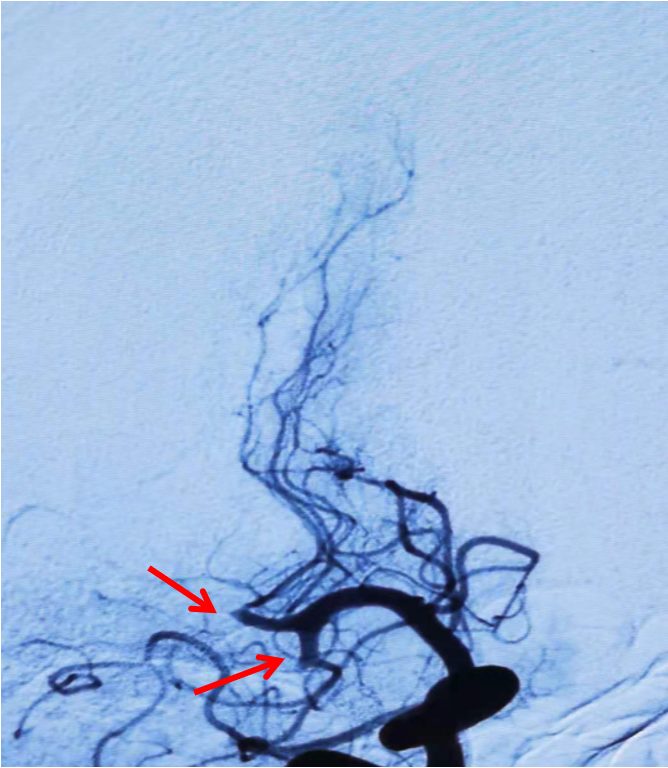

Headway17微导管在3m的Synchro-14导丝辅助下,谨慎通过闭塞处(左图箭头示),撤出微导丝,微导管造影证实在在闭塞远端血管真腔(右图箭头示)。